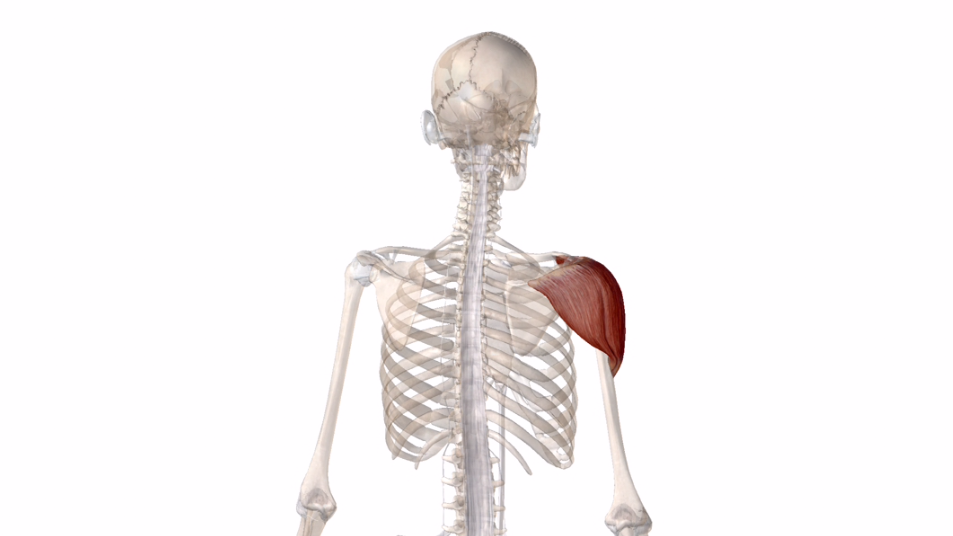

三角筋↓